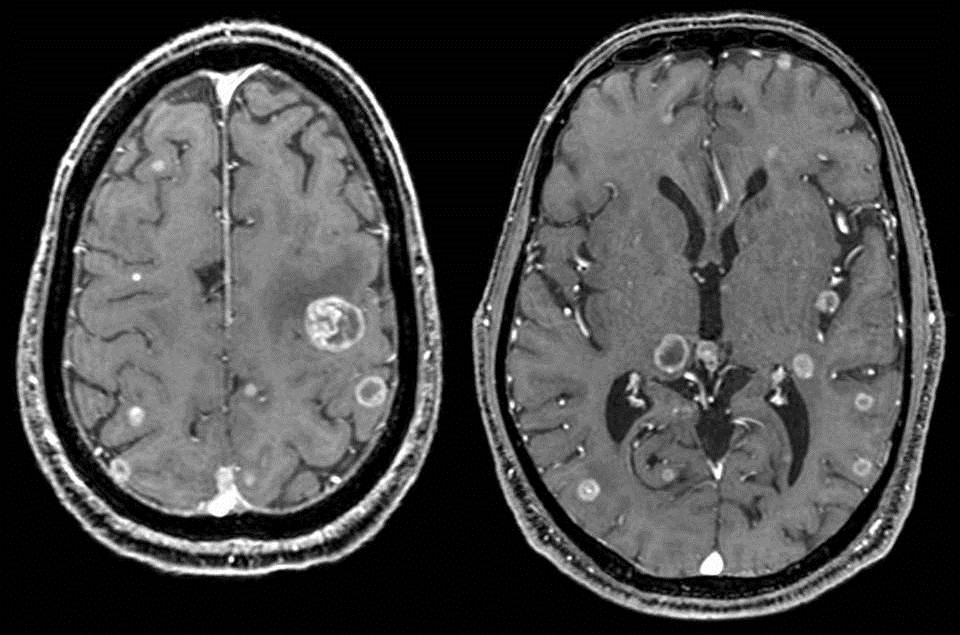

Các dấu hiệu ung thư di căn não có thể khác nhau dựa trên vị trí, kích thước, số lượng và tốc độ phát triển của các khối u.

- Số lượng và kích thước của khối u não di căn

Theo thống kê, tiên lượng sống trung bình của những bệnh nhân ung thư di căn não thường là dưới 6 tháng. Tuy nhiên, khoảng 8,3% bệnh nhân có thể sống thêm 1 năm và 1,4% sống thêm được 2 năm sau chẩn đoán. Điều trị bằng phương pháp xạ trị toàn bộ não có thể giúp tăng thời gian sống cho bệnh nhân lên đến 11 tháng.